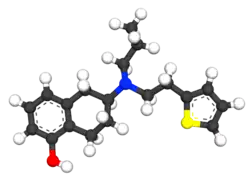

| 3D model (JSmol) | |